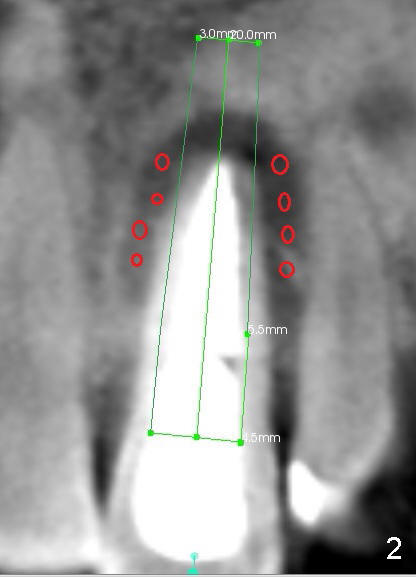

The 46-year-old patient is pleased with previous implant placement. Preop PA shows severe periapical radiolucency of the tooth #9 (Fig.1). CBCT confirms the lesion extent (Fig.2,3). It appears that the labial plate is completely lost (Fig.3). A long implant is indicated. Due to insertion into the palatal bone, an angled abutment is anticipated (20 or 30°). Prior to implant placement, bone graft is placed to the apical half of the socket (mesial and distal (Fig.2) and labial (Fig.3 red circles). How does it get done?